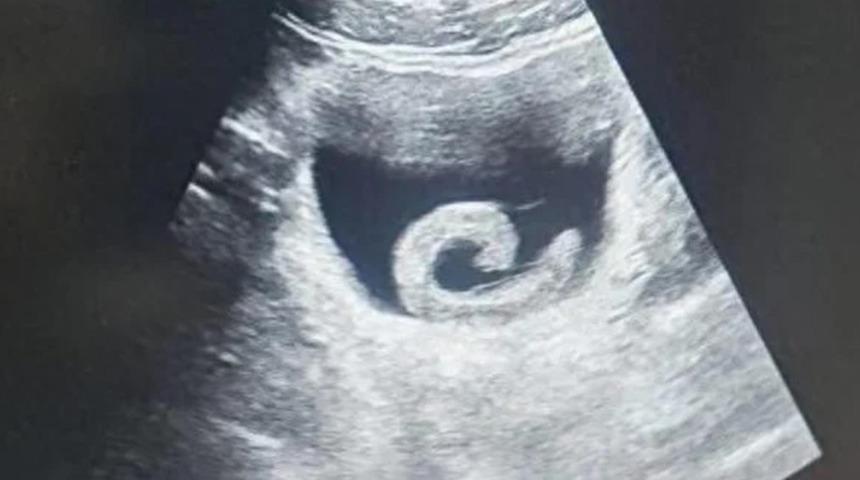

Sülük, Zheng'e o kadar dayanılmaz bir acı vermişti ki, yerel bir hastanenin acil servisine başvurmaktan başka çaresi kalmamıştı. Vaka karşısında doktorlar bile anlattıklarını duyunca şok oldular. Ultrason muayenesi, gerçekten de mesanesinde bir sülük olduğunu doğruladı ve doktorlar paraziti çıkarmak ve gencin hayatını kurtarmak için acil bir ameliyata hazırlandılar.